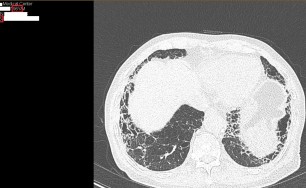

기관지확장증의 CT 사진

비결핵항산균에 감염된 폐사진